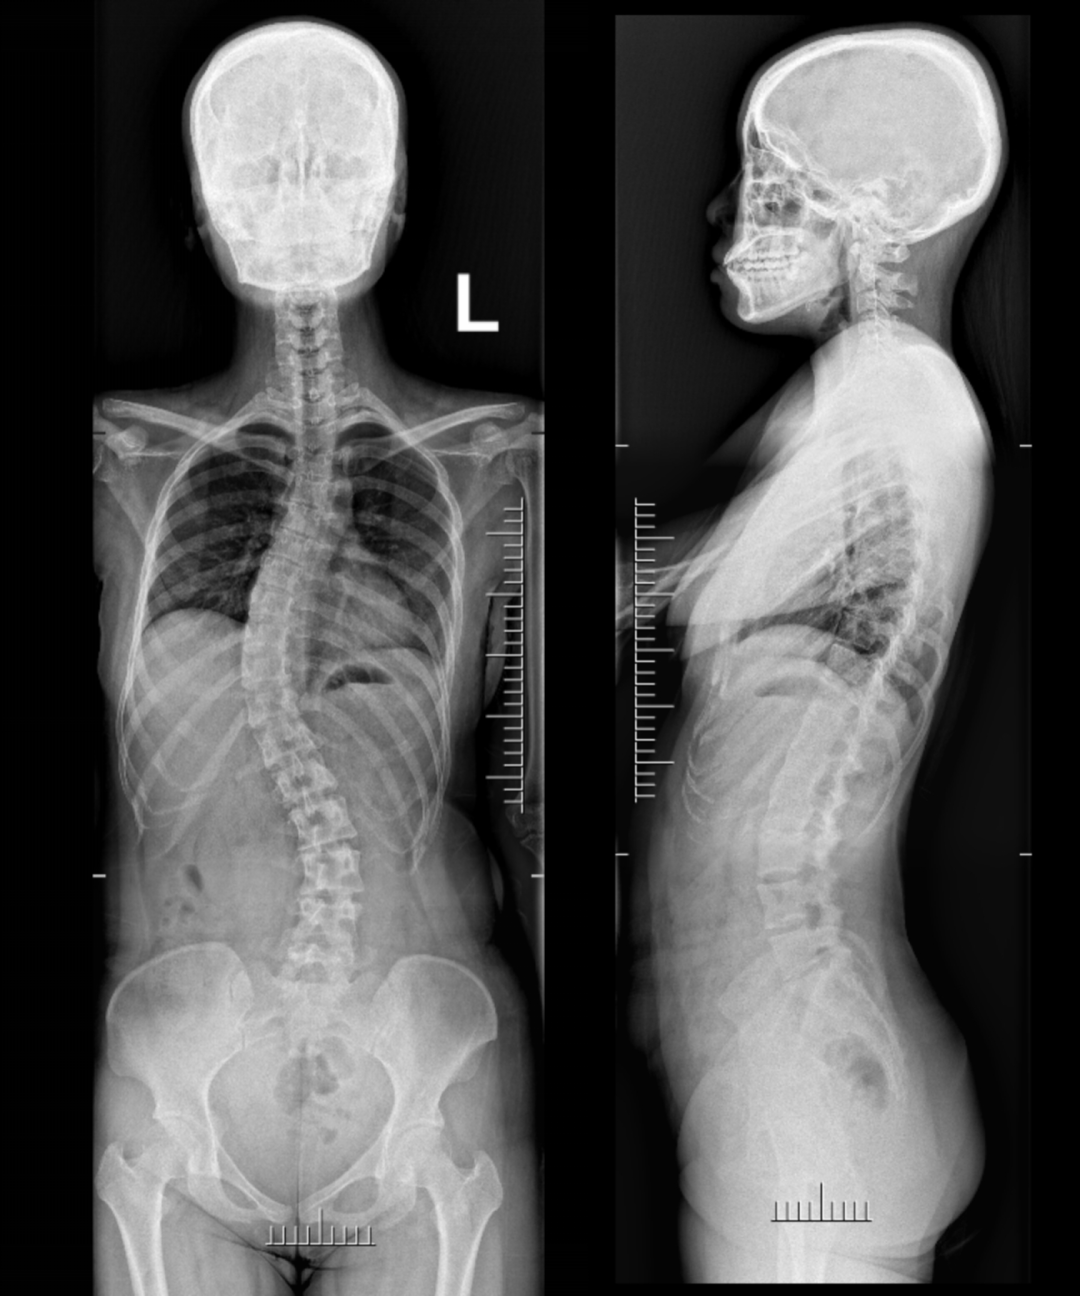

术前影像资料

X线检查

主诉:发现脊柱侧弯2年余

现病史:患者缘于2年前体检发现脊柱侧弯,未行特殊治疗,今为矫形,就诊于河北医科大学第三医院脊柱科,行脊柱全长及bending位检查,诊断为“成人脊柱侧凸”,遂住院治疗。

关键查体:剃刀背畸形,腰椎前屈后伸及左右侧屈活动稍受限,腰后部压、叩痛(-)。双下肢肌力V级,肌张力不高,感觉未查及明显异常。双侧膝腱、跟腱反射正常存在,双侧Babinski’s征(-),双侧Hoffmann’s征(-)

疾病诊断:成人脊柱侧凸